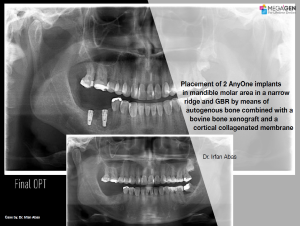

e.g. product name, treatment solution, author, clinician name